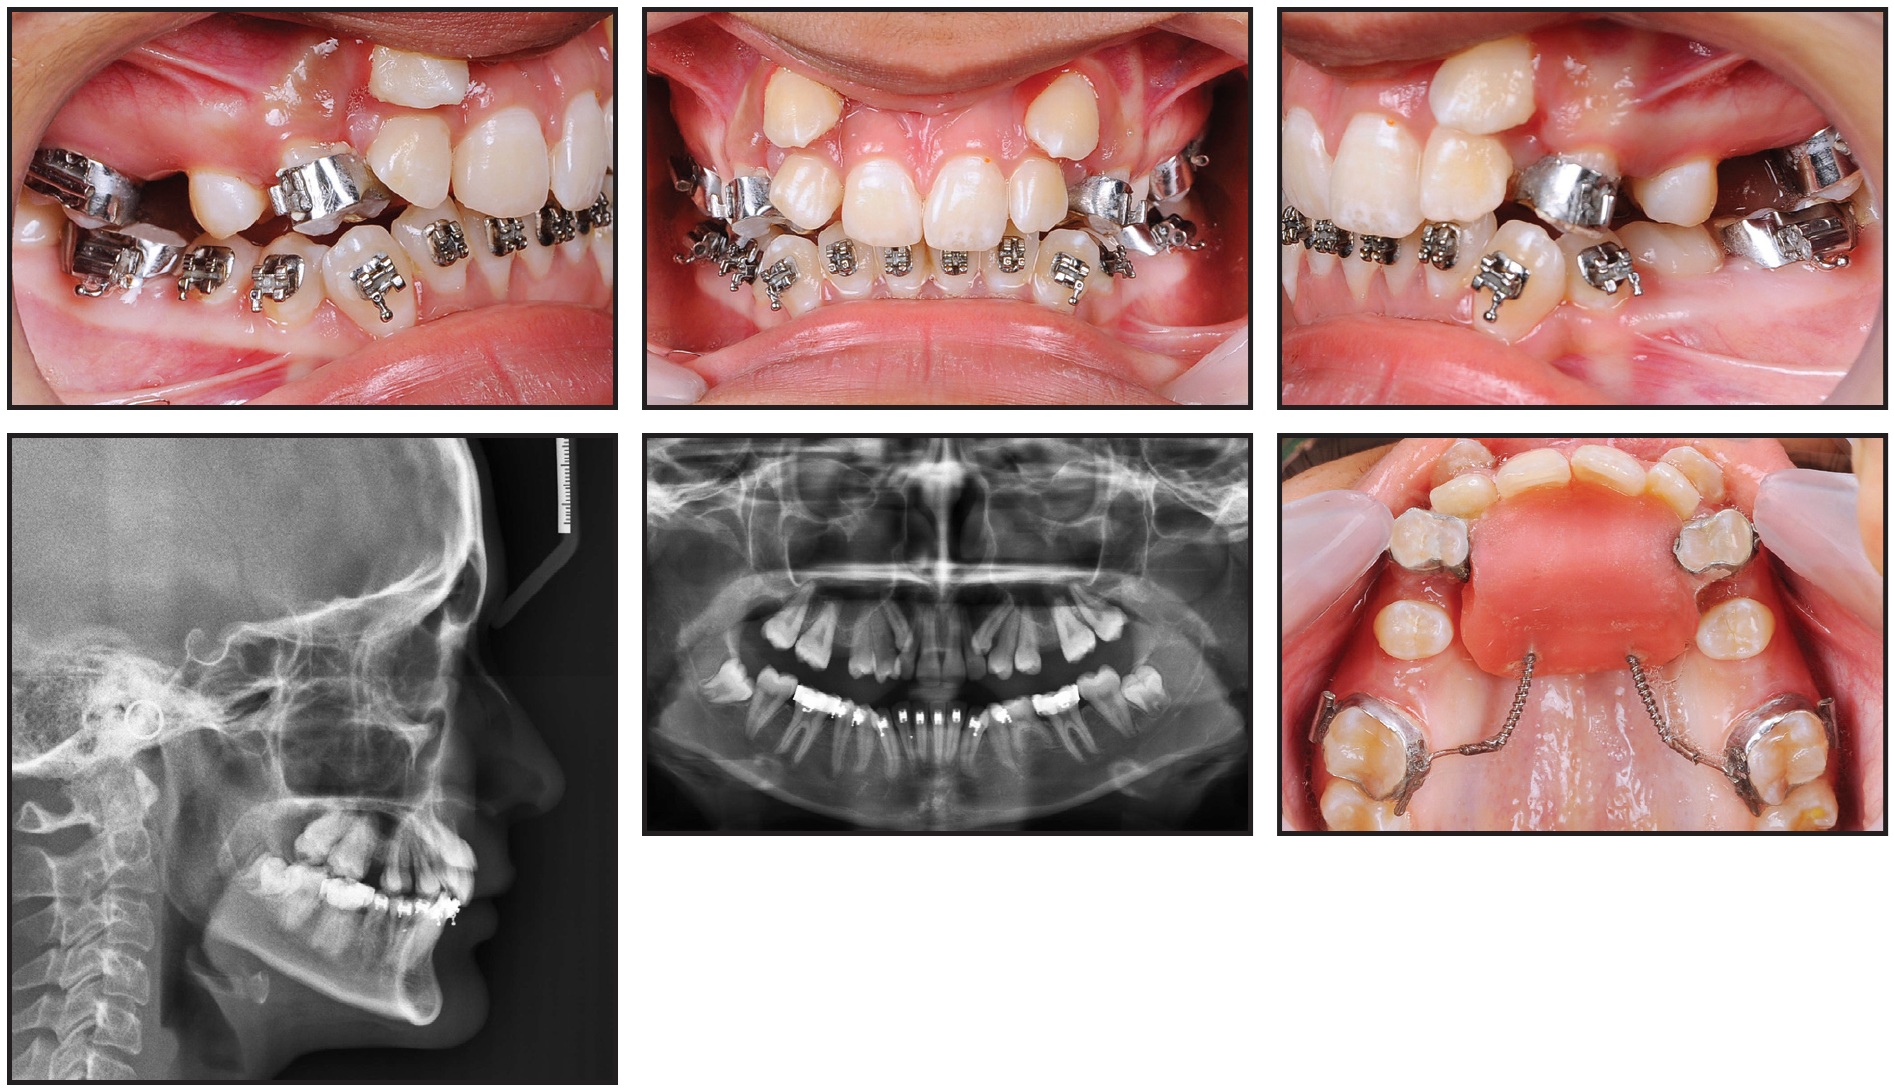

A 13-year-old female presented with highly placed, blocked-out upper canines, severe crowding in the upper arch and mild crowding in the lower, competent lips, a non-consonant smile arc, and a straight soft-tissue profile (Fig. 6).

Fig. 6 Case 2. 13-year-old female patient with Class II molar relationship, blocked-out upper canines, severe upper crowding, and mild lower crowding before treatment.

Cephalometric analysis showed a Class II molar relationship on a Class I skeletal base, owing to an orthognathic maxilla and an average mandibular growth pattern (Table 2).

The patient was treated as described in Case 1. After six months of Phase I distalization (Fig. 7), the upper arch was bonded and .014" nickel titanium archwires were inserted.

Fig. 7 Case 2. After six months of distalization.

Treatment continued over 14 months, finishing with .019" × .025" TMA† archwires and positive canine torquing.

Fig. 8 Case 2. Patient after 19 months of treatment.

Retention involved upper and lower 3-3 fixed lingual wires and upper and lower Hawley retainers. The results remained stable when evaluated 29 months after treatment (Fig. 9).

Fig. 9 Case 2. Patient 29 months after treatment.